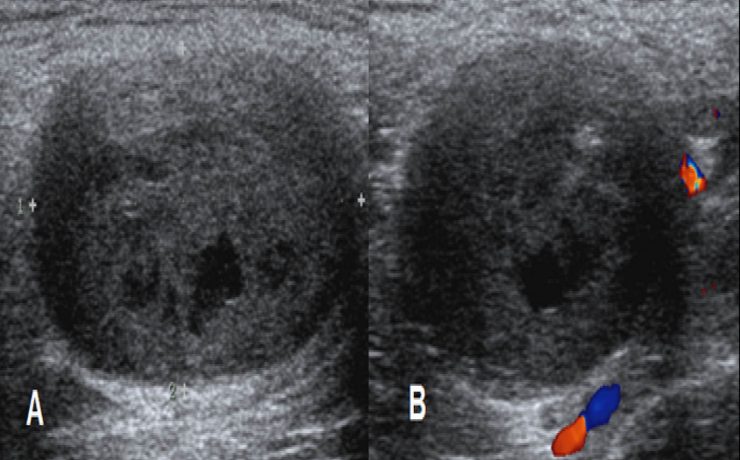

La incidencia de coledocolitiasis después de la intervención quirúrgica tiene una incidencia del 10 porciento, Los cálculos pueden permanecer por años dentro de la vía extra hepática y no manifestar síntomas. Los cálculos pequeños pueden pasar por el colédoco y el duodeno sin producir síntomas (menores 3mm), solo que se